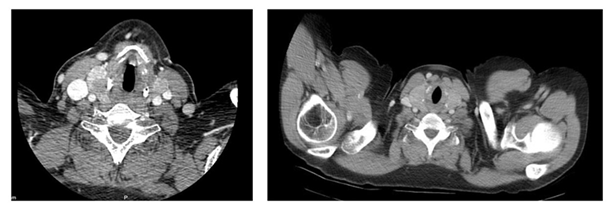

The computed tomography (ct) showed an increase in the size of the thyroid with an estimated volume of 100 cc, with intrathoracic extension at the expense of multiple nodules. The largest one was 35 mm, with a cystic appearance, with macrocalcifications located in the ld, which correlates with the ultrasound description. Extrinsic compression was determined in the upper third of the trachea, with a residual lumen of 3 mm x 14 mm

(figures 2 and 3).

Figure 2: ct, axial section showing substernal goiter with displacement and narrowing of the tracheal lumen and the esophagus

Figure 3: ct, coronal section in which a large multinodular goiter with a cystic area is observed and in the image on the right tracheal light compression with an "hourglass" image